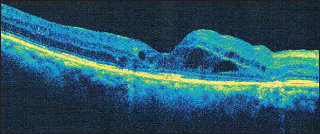

My first example of successful use of MPLT is with a 63-year-old white male with very aggressive refractive DME (Figure 1). I had administered multiple injections of bevacizumab (Avastin, Genentech, South San Francisco, CA) and triamcinolone (Triesence, Alcon, Forth Worth, TX) ) and one injection of dexamethasone (Ozurdex OS, Allergan, Irvine, CA), with very little response.

Figure 1.This is 63-year-old man had very aggressive refractory DME that would not respond to anti-VEGF or steroid.

I decided to perform laser photocoagulation with the Iridex IQ 532 (Iridex, Mountain View, CA) in micropulse emission mode. My laser settings were 550 mW of power, 200 msec, 5% duty cycle, and 100-μm spot size with heavy confluence around the macular area. At baseline, the patient had central retinal thickness of 438 μm as seen on OCT and visual acuity of 20/200.